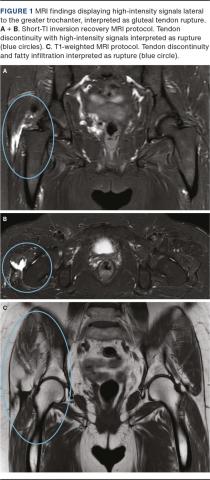

As the presence of isolated bursitis of the greater trochanter was the primary purpose of this study, a consensus meeting was held after finalization of the individual evaluations of the 120 MRIs. At this meeting, CT and JL evaluated 49 MRI in which one or the other had interpreted the presence of bursitis with or without the presence of concomitant HATP (see Figure 2 for an example), and a consensus on the final evaluation was registered. We registered HATP on a binary level. HATP included tendinopathies, tendon tears or tendon ruptures without distinguishing between these.

Other conceptual findings were registered according to Table 1 (see Figure 2).

Two (2%) patients had isolated greater trochanteric bursitis with no associated HATP. Thirty (25%) patients had HATP with some elements of inflammation (high-intensity signals) in the greater trochanteric bursa (as an example of this, see Figure 2). Five (4%) patients had HATP with bursitis in the sub-gluteus minimus bursa with no bursitis in the greater trochanteric bursa. The remaining patients (69%) had no high-intensity signals indicating trochanter-related bursitis.

A total of 88(93%) patients had a Kellgren-Lawrence grade ≤ 1 on X-ray. Four patients (4%) had calcifications lateral to the greater trochanter on X-ray (see Figure 2).